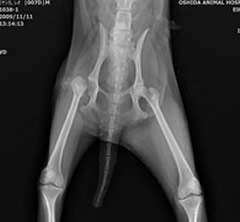

術後:レッグ・ペルテス

無菌性大腿骨頭壊死症

疼痛から患肢を使っていなかったため、筋肉量に明らかな差が認められましたが、骨頭切除術後は運動量とともに筋肉量も増加してきました。